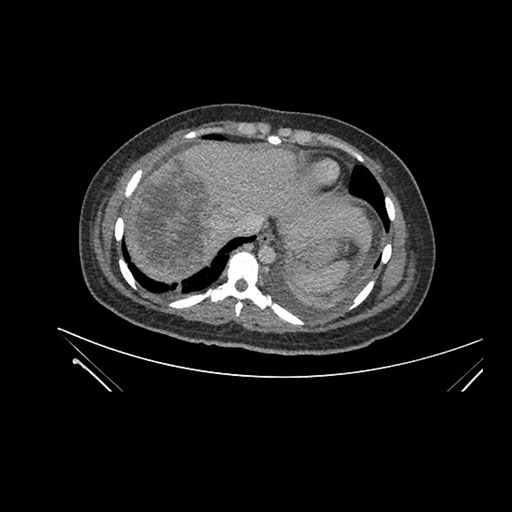

Axial Arterial

Axial Venous